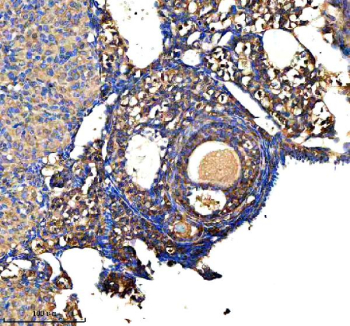

Immunohistochemical staining of GSTM2 using anti-GSTM2 antibody. GSTM2 was detected in a paraffin-embedded section of mouse ovary tissue. Heat mediated antigen retrieval was performed in EDTA buffer (pH 8.0, epitope retrieval solution). The tissue section was blocked with 10% goat serum. The tissue section was then incubated with 2 ug/ml rabbit anti-GSTM2 antibody overnight at 4oC. Peroxidase Conjugated Goat Anti-rabbit IgG was used as secondary antibody and incubated for 30 minutes at 37oC. The tissue section was developed using an HRP secondary and DAB substrate.